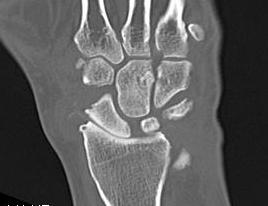

X-ray

OA radio-scaphoid joint

Preservation of radiolunate joint